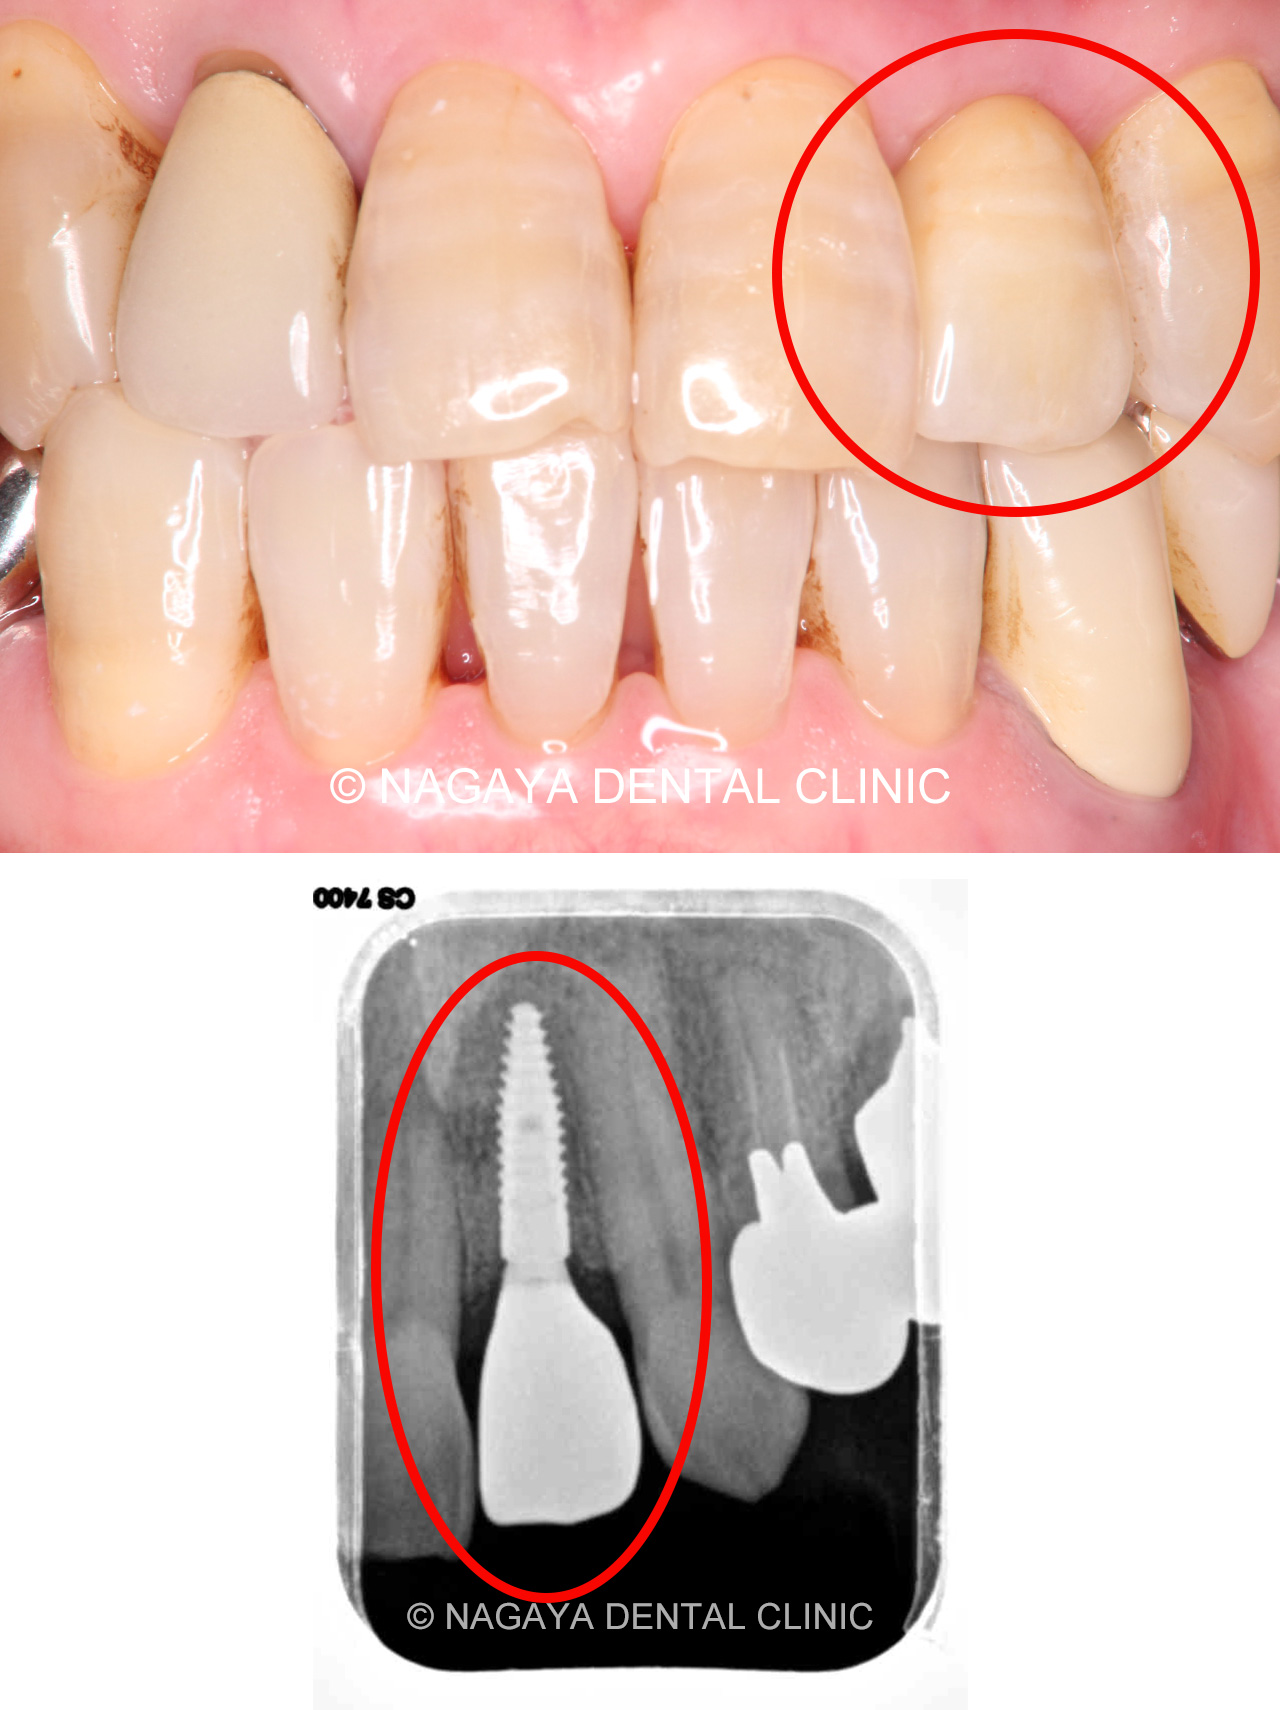

| 主訴 | インプント治療を受けたい |

| 治療方法 | インプラント |

| 治療の説明 | 他院で抜歯を行った後、入れ歯を勧められましたが、入れ歯には抵抗があり、他の治療方法を探されていました。 その結果、当院でインプラント治療を希望されました。 患者様のご希望により、歯の欠損部分をインプラントで補い、上部構造(被せ物)にはフルジルコニアセラミックのブリッジを選択されました。 そのため、見た目や噛み心地がより天然歯に近い仕上がりとなりました。 |

| 治療期間 | 5ヵ月 |

| 副作用(リスク) | インプラント手術後は、出血、腫れなどがおきる場合がありますが、時間経過とともに治癒します。 また、喫煙、糖尿病、加齢、清掃不良などに伴いインプラント周囲の骨に炎症が起こり、再治療が必要になるケースがあります。 |